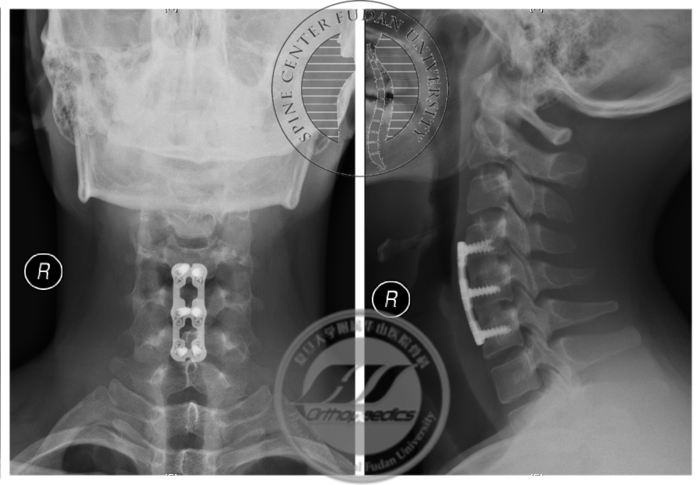

患者于2017年8月30日接受颈椎前路自体髂骨植骨融合内固定术,术后恢复良好,定期随访。最近一次随访为2019年9月(术后2年),患者诉右手握力较前增大,寒冷时症状较前好转,伸指震颤症状仍存在。X线示内固定无松动移位,屈颈位MRI显示“膜-壁分离”现象消失,屈颈位脊髓未见明显压迫,相邻节段未见明显退变(图6,7),神经电生理检查示所检肌自发电位消失,募集较前好转(图8)。

图6 术后2年X线示内固定无松动移位,颈椎曲度良好